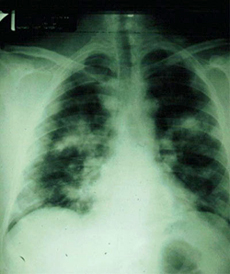

Pneumonic plague, x-ray foto |